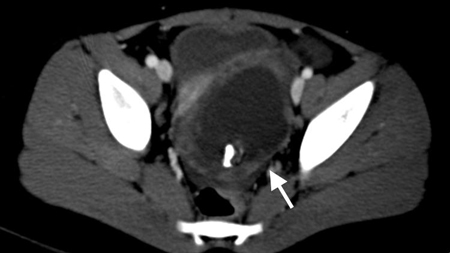

- tomografia computadorizada (TC) de abdome e pelve:

lesão em alvo: massa intraluminal de tecido mole, com uma área de gordura excentricamente posicionada; massa reniforme: alta atenuação periférica e atenuação central mais baixa; massa em forma de salsicha: áreas alternadas de baixa e alta atenuação representando a parede intestinal menos espaçada, gordura mesentérica e/ou fluido e gás intestinal